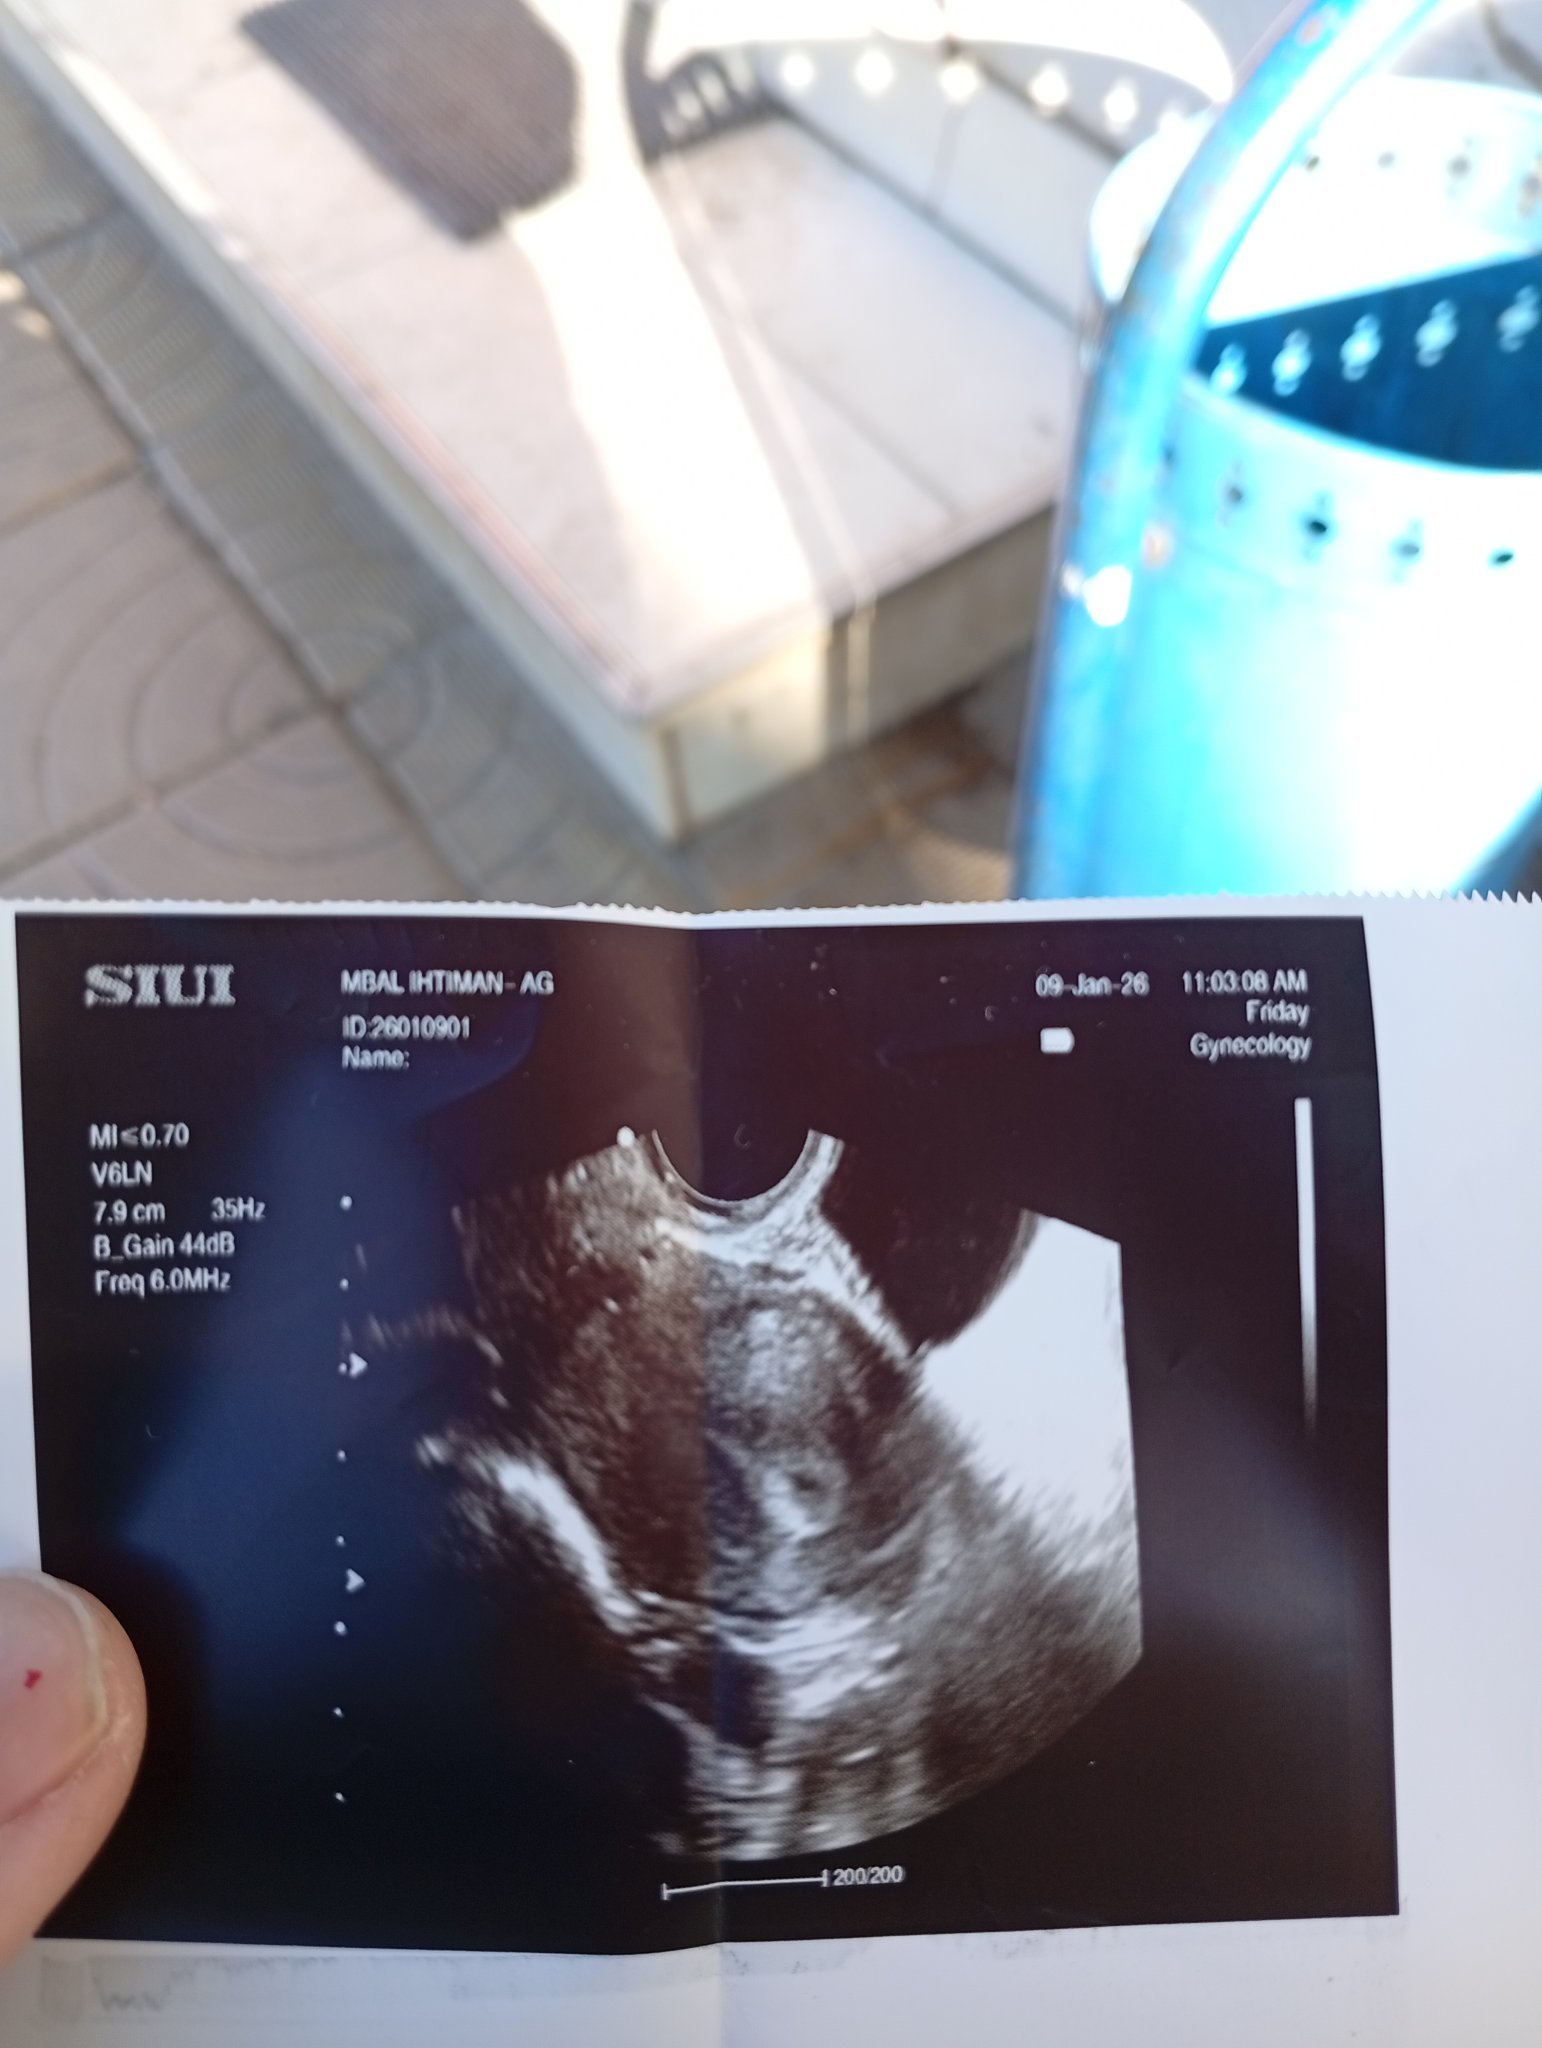

Здравейте! Има ли как тези черти да са от остатъчно чхг след спонтанен аборт?

Вече съм месец след аборта, случи се самостоятелно, без намеса от лекари на 15.12. На 28.12 имахме полов контакт(след позволение от лекар). На 11.01 направих горният тест към 20:00ч, тъй като не се чувствах много добре, отпадналост, спеше ми се доста и се усъмних.  Излезе веднага много бледа черта, която по-късно потъмня. Този отдолу е направен днес, не е с първа урина.

Не съм имала първа менструация след аборта.

Здравейте, това са резултатите от кръвният.